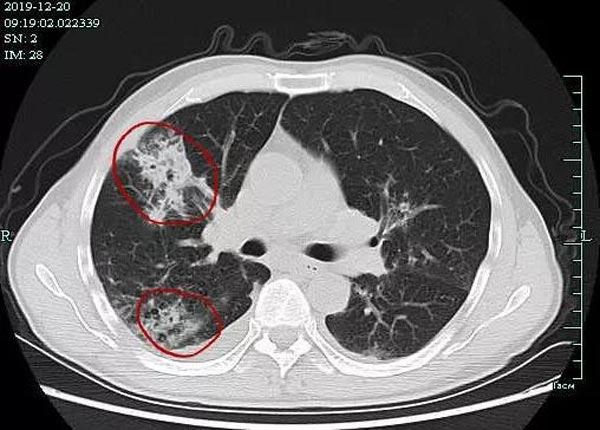

Ông Shao liên tục ho ra đờm vàng, cơ bắp đau nhức. Vợ con ông nhận thấy ông có vẻ ốm yếu nên đã nhanh chóng đưa ông đến bệnh viện địa phương. Kết quả chụp CT ngực phát hiện bất thường, bác sĩ đã tiến hành nội soi phế quản cho ông và thấy rằng có một lượng lớn dịch tiết màu vàng và trắng trong khoang phế quản. Vì vậy, bác sĩ cần xét nghiệm thêm trước khi đưa ra chẩn đoán chính xác.

Phim chụp X-quang phổi cho thấy nấm mốc phát triển trong cơ thể ông Shao.

7 ngày sau, kết quả nuôi cấy dịch phế quản cho thấy có sợi nấm aspergillus xuất hiện trong phổi, điều đó có nghĩa là trong cơ thể ông Shao có nấm phát triển và sinh sản trong cơ thể, xác nhận rằng ông đã bị nhiễm nấm Aspergillus .

Sau khi nhập viện vài ngày, kết quả CT phổi cho thấy tình trạng bệnh của ông vẫn đang tiến triển. Nếu không được điều trị ngay, ông Shao có thể sẽ bị suy hô hấp và thậm chí đe dọa đến tính mạng. Ông Shao mau chóng được chuyển đến Khoa truyền nhiễm, Bệnh viện đầu tiên của Đại học Chiết Giang để tiếp tục điều trị.